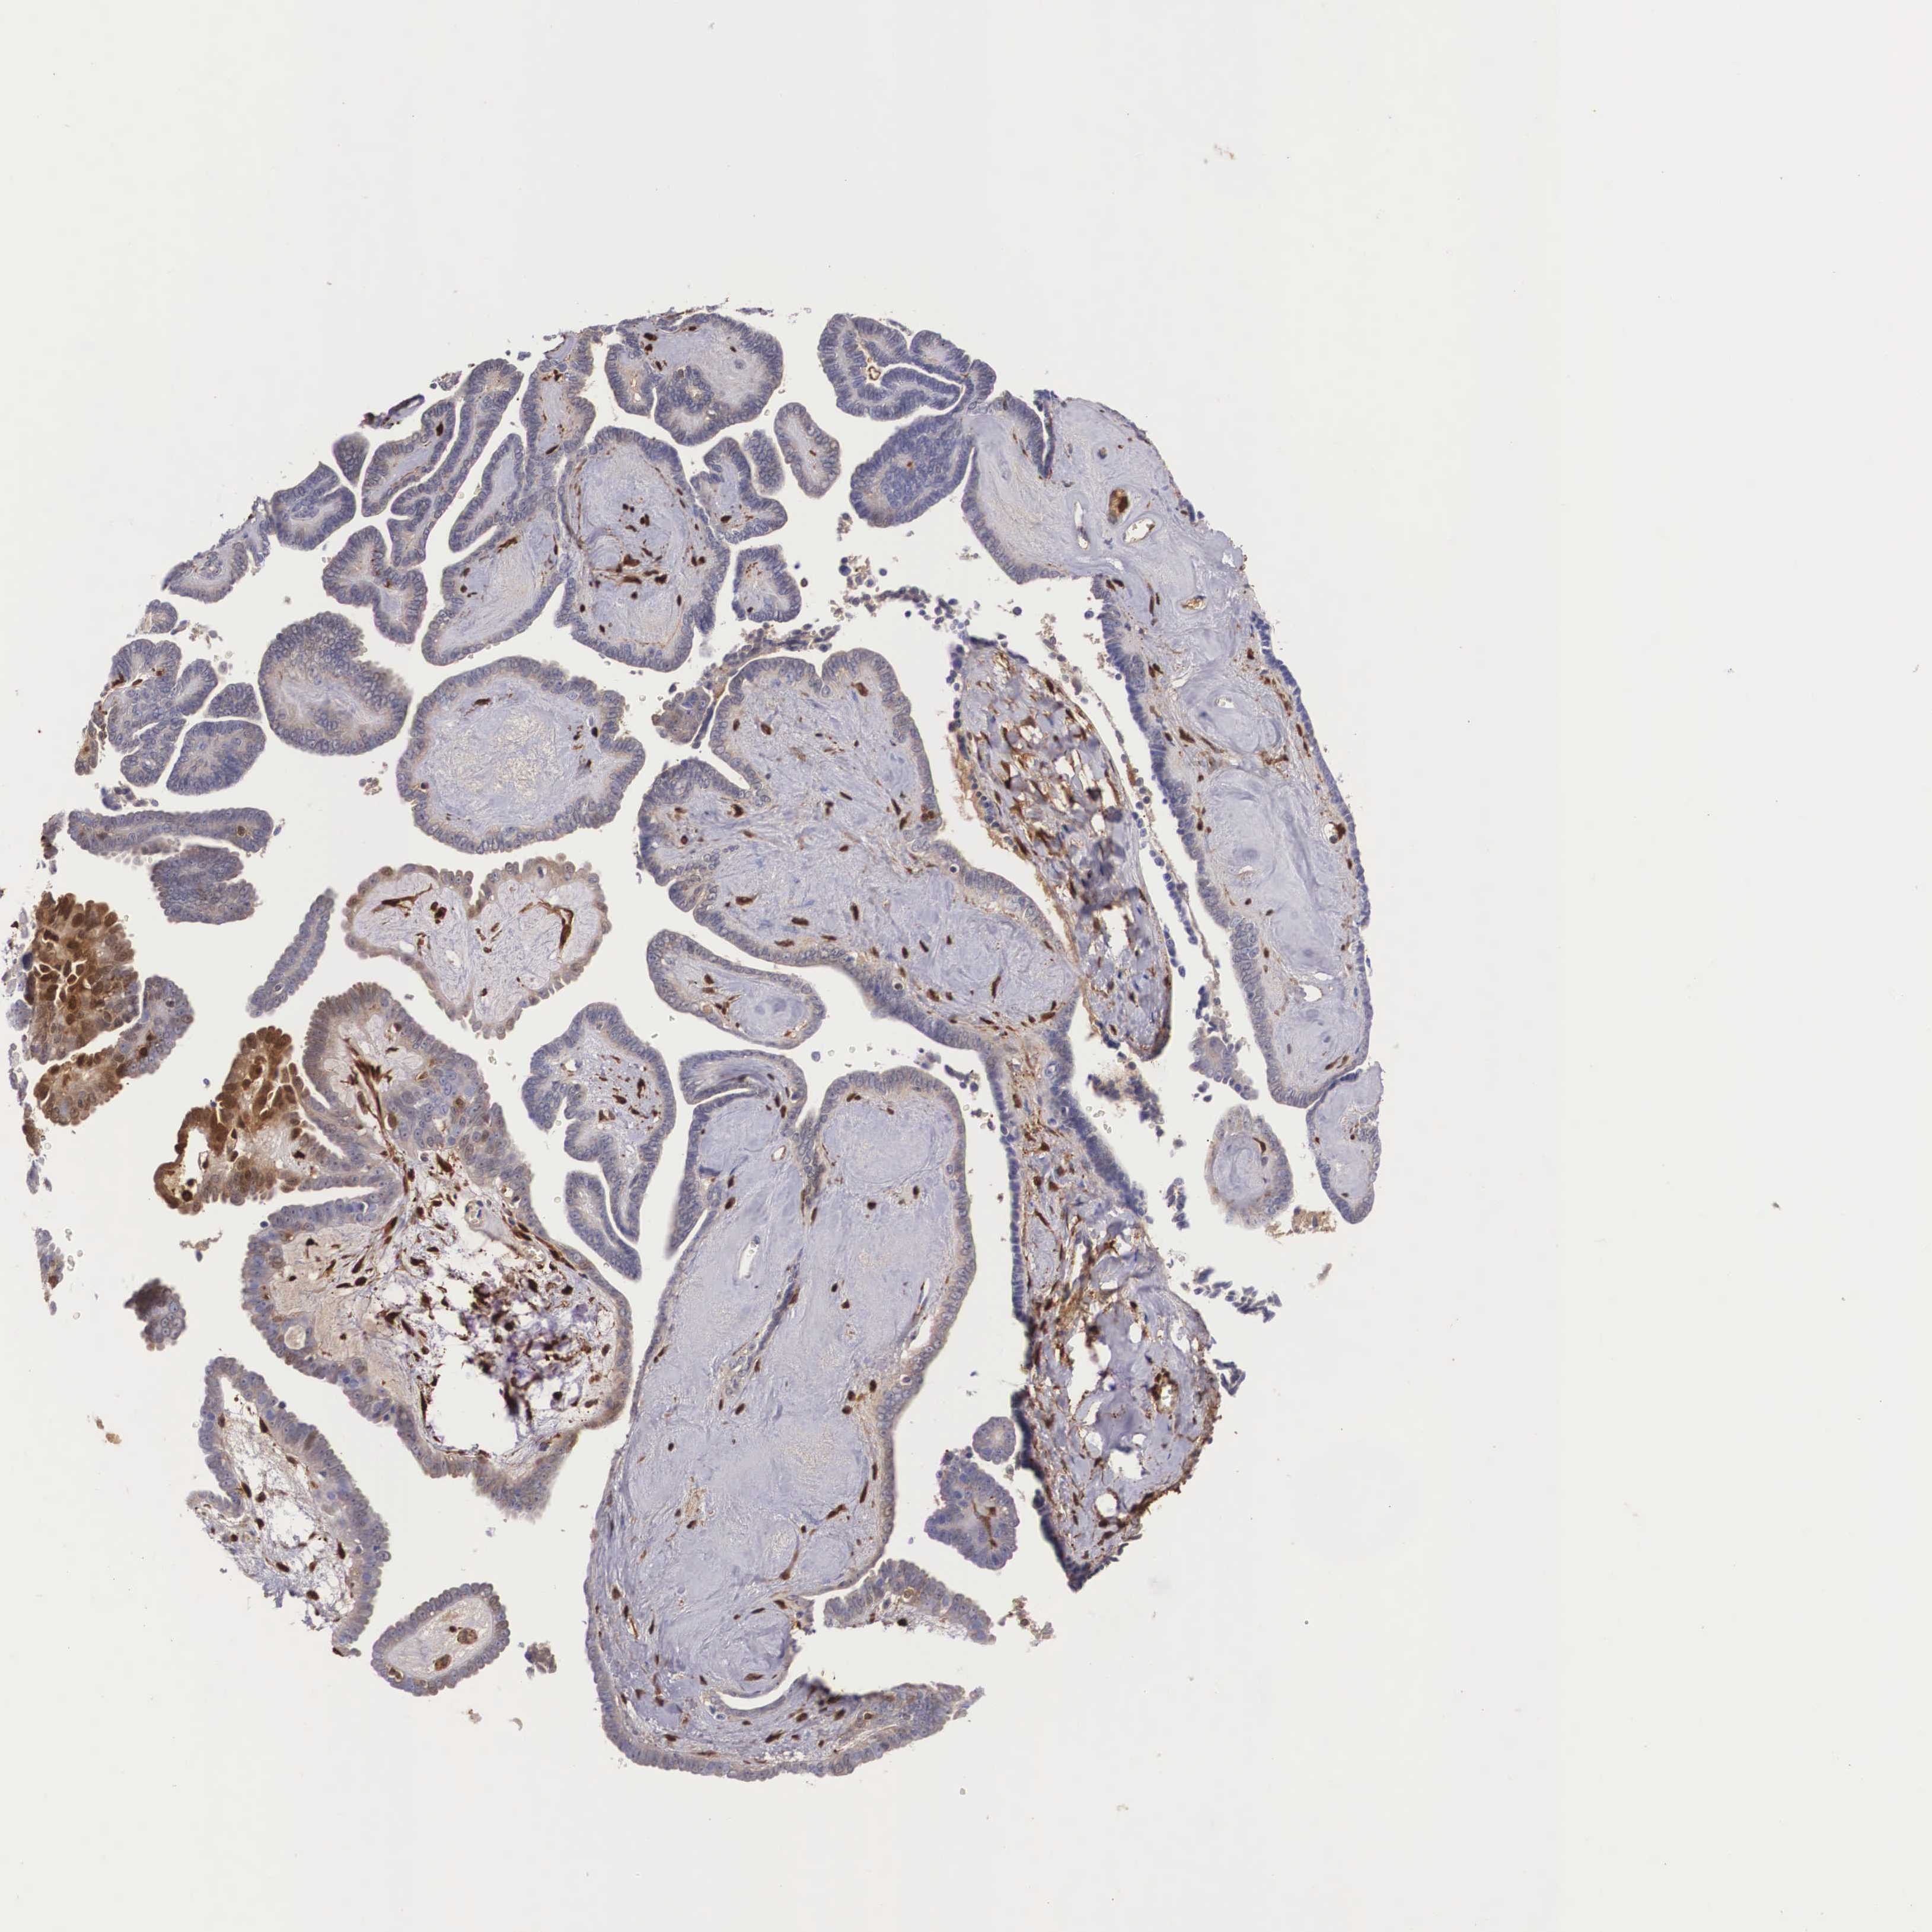

OVARIAN CANCER - Protein expressioni

A mouse-over function shows sample information and annotation data. Click on an image to view it in a full screen mode. Samples can be filtered based on level of antibody staining by selecting one or several of the following categories: high, medium, low and not detected. The assay and annotation is described here.

Note that samples used for immunohistochemistry by the Human Protein Atlas do not correspond to samples in the TCGA dataset.

Antibody stainingi

Antibody staining in the annotated cell types in the current human tissue is reported as not detected, low, medium, or high, based on conventional immunohistochemistry profiling in selected tissues. This score is based on the combination of the staining intensity and fraction of stained cells.

Each image is clickable and will lead to virtual microscopy that enables deeper exploration of all samples and also displays staining intensity scores, fraction scores and subcellular localization as well as patient and tissue information for each sample.

Antibody CAB002157

Carcinoma, endometroid

Cystadenocarcinoma, mucinous, NOS